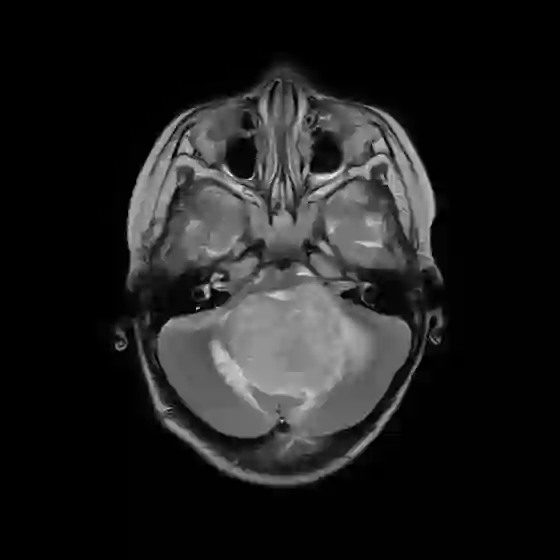

The field of explainability in artificial intelligence has witnessed a growing number of studies and increasing scholarly interest. However, the lack of human-friendly and individual interpretations in explaining the outcomes of machine learning algorithms has significantly hindered the acceptance of these methods by clinicians in their research and clinical practice. To address this, our study employs counterfactual explanations to explore "what if?" scenarios in medical research, aiming to expand our understanding beyond existing boundaries on magnetic resonance imaging (MRI) features for diagnosing pediatric posterior fossa brain tumors. In our case study, the proposed concept provides a novel way to examine alternative decision-making scenarios that offer personalized and context-specific insights, enabling the validation of predictions and clarification of variations under diverse circumstances. Additionally, we explore the potential use of counterfactuals for data augmentation and evaluate their feasibility as an alternative approach in our medical research case. The results demonstrate the promising potential of using counterfactual explanations to enhance trust and acceptance of AI-driven methods in clinical research.